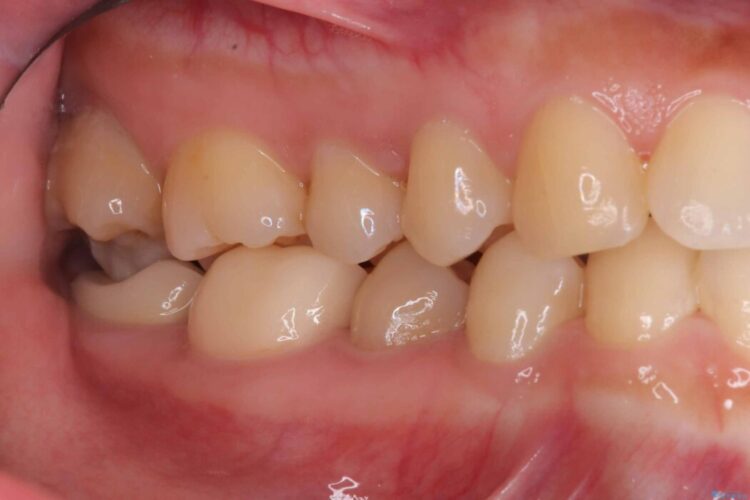

以前に詰めた白い詰め物の内部で、虫歯の再発が確認されました。